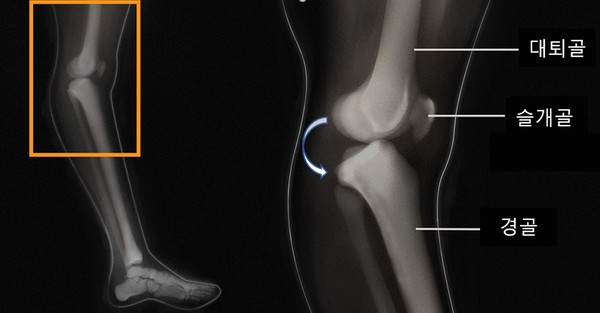

아래 그림처럼 무릎의 과신전이 발생하면, 앞쪽의 대퇴골과 경골은 충돌이 되고, 반대로 뒤쪽은 벌어지게 됩니다. 이 때 관절을 잡아주고 있는 관절막이 파열이 일어나게 됩니다. 이 상태에서 더 진행이 되지 않는다면 다행이겠지만 여기서 과신전이 더 발생하게 된다면 전방 또는 후방십자인대까지 손상을 받을 수 있습니다. 무릎이 뒤틀리는 경우는 드믈기 때문에 반월판 연골의 손상은 없는 경우가 많습니다.